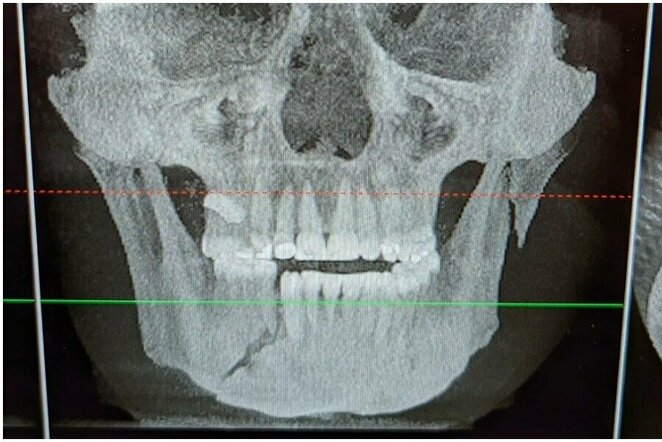

Rentgeno nuotrauka | Instagram.com nuotr

A.Polizzi neseniai pasidalino rentgeno nuotraukomis po kovos. Jose matyti, kad Y.Romero smūgiai sulaužė varžovo žandikaulį.